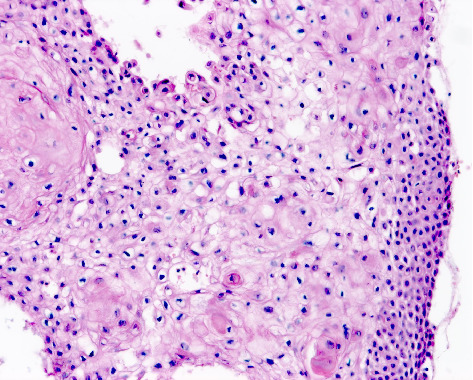

背景:皮肤鳞状细胞癌(CSCC)是全球第二常见的皮肤癌。然而,在澳大利亚和美国等国家,其发病率相对于基底细胞癌(BCC)正在上升。在南非,人口暴露于许多CSCC风险因素,包括高紫外线辐射水平和免疫抑制的高负担,在这方面描述该疾病特征的科学文献仍然明显缺乏。目的:描述南非队列中CSCC的临床、组织病理学和风险特征,以确定可以为当地临床实践提供信息的模式,并指导未来的研究重点。方法:对2019年9月1日至2020年8月31日在Tygerberg学术医院就诊的患者进行回顾性数据分析。从医疗记录中提取人口统计学和临床数据。两名研究评估人员使用预先确定的标准来审查皮肤活检的组织病理学特征。病变的风险分层遵循国家综合癌症网络的指导方针。结果:在一年多的时间里,83例患者诊断出113例CSCCs。参与者主要为Fitzpatrick皮肤光型I(65.1%)和男性(60.2%),中位年龄为73岁,男女比例为1.51:1。bcc与cscc的发病率比为1.71:1。大多数病变存在超过6个月(87.6%),位于头颈部(59.3%)。穿刺活检诊断出62.8%的病变。组织学上63.7%为高分化,40.7%为浸润性。常规CSCCs占病变的75.2%;5.3%为棘溶性高危亚型。77.0%的病变有高复发风险。结论:本研究突出了南非CSCC的异质性,强调了前瞻性、具体情况研究的必要性,以加强全国范围内的预防、早期发现和管理工作。

Background: Cutaneous squamous cell carcinoma (CSCC) is the second most prevalent form of skin cancer globally. However, its incidence is rising relative to basal cell carcinoma (BCC) in countries such as Australia and the United States. In South Africa, where the population is exposed to numerous CSCC risk factors, including high ultraviolet radiation levels and a high burden of immunosuppression, there remains a notable paucity of scientific literature characterising the disease within this context. Aims: To describe the clinical, histopathological and risk profile characteristics of CSCC in a South African cohort to identify patterns that can inform local clinical practice and guide future research priorities. Methods: A retrospective data analysis of patients seen at Tygerberg Academic Hospital between 1 September 2019 and 31 August 2020 was conducted. Demographic and clinical data were extracted from medical records. Two study evaluators used predetermined criteria to review the histopathological features in skin biopsies. Risk stratification of lesions followed the guidelines of the National Comprehensive Cancer Network. Results: Over one year, 113 CSCCs were diagnosed in 83 patients. Participants were primarily Fitzpatrick skin phototype I (65.1%) and male (60.2%), with a median age of 73 years and a male-to-female ratio of 1.51:1. The BCC-to-CSCC incidence ratio was 1.71:1. Most lesions had been present for over 6 months (87.6%) and were located on the head and neck (59.3%). Punch biopsies diagnosed 62.8% of lesions. Histologically, 63.7% were well differentiated, and 40.7% were invasive. Conventional CSCCs comprised 75.2% of lesions; 5.3% were the high-risk acantholytic subtype. A high recurrence risk was found in 77.0% of lesions. Conclusion: This study highlights the heterogeneous nature of CSCC in South Africa and underscores the need for prospective, context-specific research to enhance prevention, early detection and management efforts nationwide.